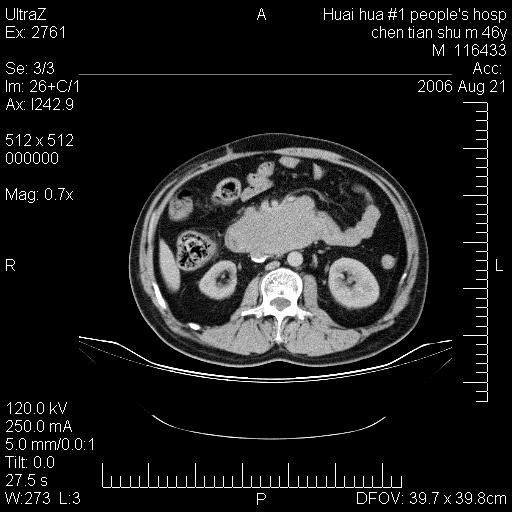

患者,男,46y。腹痛2月,消瘦。

十二指肠水平段占位,考虑间质瘤或平滑肌瘤。

肿块较大,腹膜后占位,境界欠清,周边脂肪密度较高呈条状影,有没有脂肪肉瘤可能,

缺少完整的三期图像。考虑肠系膜脂膜炎mp(肿块型)。

鉴别:间质瘤(这么大而无囊变不可思议)、平滑肌瘤/肉瘤、淋巴瘤、类癌,脂肪类肿瘤、转移瘤等。

十二指肠水平段占位,考虑间质瘤。

首先考虑小肠间质瘤。

十二指肠水平段软组织密度占位,考虑间质瘤可能性大。

腹膜后占位,境界欠清,考虑来源于十二指肠病变,间质瘤或平滑肌肉瘤可能性大。建议活检。

手术病理结果:原发性小肠恶性淋巴瘤(primary gastrointestinal lymphoma,pgil)是原发于胃肠的淋巴网织系统的恶性肿瘤,在结外淋巴瘤中居第一位,该病少见,临床无特异性,诊断困难,术前主要依靠影像学诊断。胃肠道本身具有较丰富的淋巴组织,因而胃肠原发性淋巴瘤是结外淋巴瘤最常见的部位,文献报道约占胃肠道恶性肿瘤的1%~4%,其中胃约占50%~70%,小肠约占35%~70%,结肠约占4%~6%。影像检查在pgil的诊断及分期中有重要的作用,ct是很有价值的检查方法。

胃肠淋巴瘤病理特点:胃肠道原发性淋巴瘤起源于胃肠壁固有层和黏膜下层的淋巴组织即胃肠粘膜相关淋巴组织(malt),多为粘膜相关淋巴瘤。病理上通常为非霍奇金淋巴瘤,且决大多数来源于b淋巴细胞,很少见于霍奇金淋巴瘤。胃肠原发淋巴瘤比胃肠道癌的发病率要低的多,最常见于胃,其病因可能跟幽门螺杆菌感染有关。幽门螺杆菌能引起胃粘膜损害,引起炎性及免疫反应,淋巴细胞聚集并形成滤泡,可影响胃的正常生理功能,导致胃淋巴瘤的发生。单纯性小肠淋巴瘤是常见好发于回盲末端,受累的肠段较长,可单发、多发,甚至累及整个小肠。原发性大肠淋巴瘤罕见,以直肠和盲肠最多见。病变大体观可表现为胃肠腔内外的肿块,也可表现为从黏膜下到浆膜面肠壁的纵向浸润,并且常常伴有肠系膜淋巴结肿大。任何情况下,肿瘤几乎总是导致一定程度的肠壁增厚,可对称或不对称,病变与正常组织间常无明确分界,肠腔可狭窄、正常或动脉瘤样扩张,后者主要是肿瘤在肠壁内浸润,破坏肠壁内植物神经丛所致。以上改变成为ct检测病变的病理基础。

肠道淋巴瘤的ct表现分为4类

1) 壁内浸润型, (2)多发结节型, (3)肠系膜受累伴腔外肿块型(本型就是),(4)肿块型。